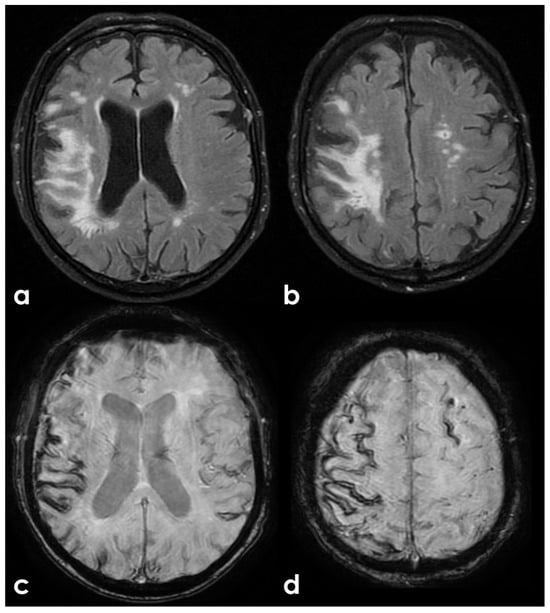

7. Structural Neuroimaging Markers